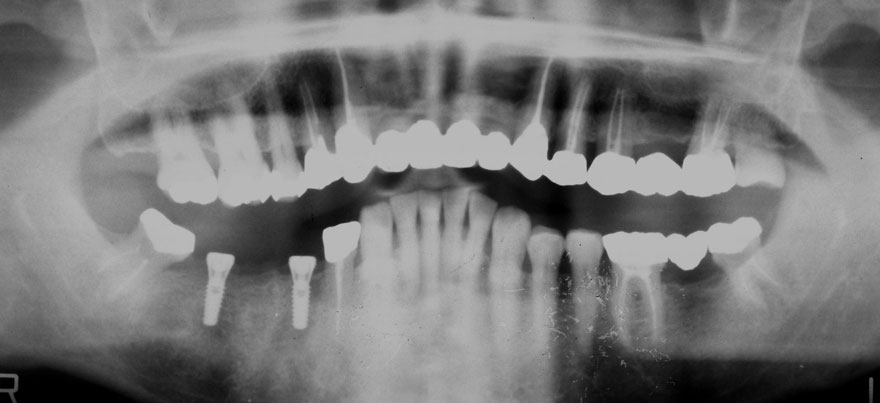

初診時 42歳 男性 平均歯槽骨喪失量:5.30mm

22年後 64歳

平均歯槽骨喪失量:5.554mm

22年間喪失量:-0.24mm

年間喪失速度:-0.01mm

(ケア頻度:1.07ヵ月ごと)